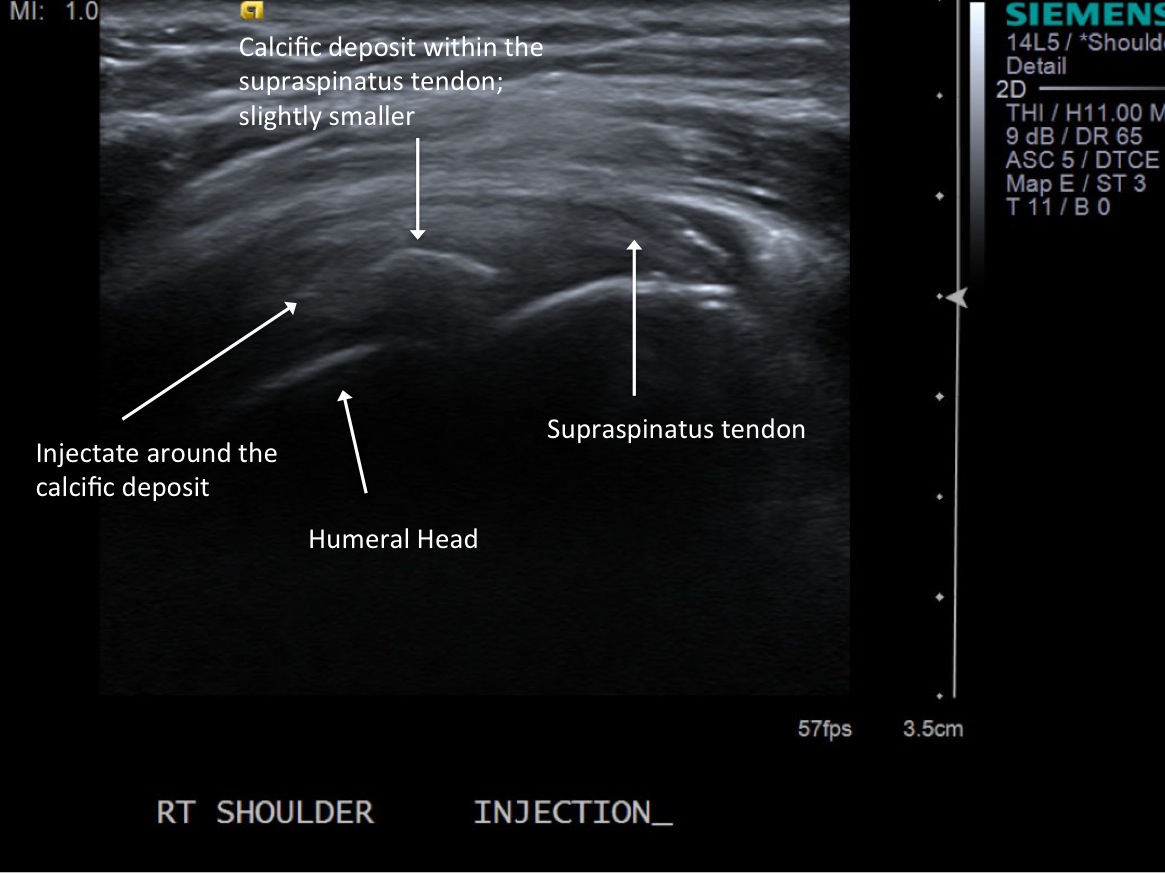

• descriptiondescription

Post procedure scan demonstrating decreased size and decreased central echogenicity of calcific deposit and injectate surrounding it.